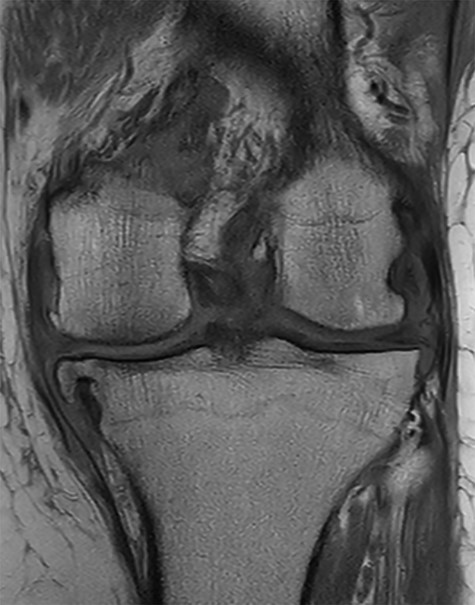

Conventional radiographs in an anteroposterior and lateral view showed advanced osteoarthritis (Kellgren stage III) accentuated medially and patellofemoral (Figs 1 and 2). An additional magnetic resonance imaging (MRI) was performed, which confirmed the medial accentuated osteoarthritis, it revealed some minor meniscal tears, some signs of general synovitis and joint effusion (Figs 3 and 4).